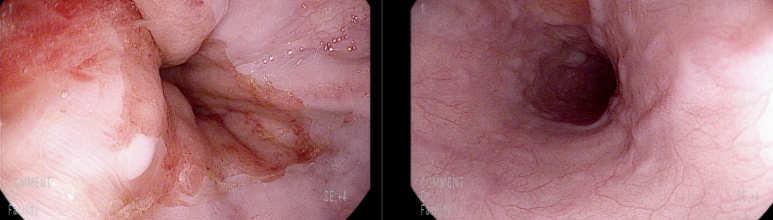

내원 다음날 위내시경 시행

F1LmCbwRCS- 소견의 정맥류 관찰됨

출혈의 흔적이 있으나 위와 십이지장에 혈액은 관찰되지 않음

검사 중 구역에 의한 출혈 관찰

위저부 후벽에 정맥류 소견

식도를 비롯하여 출혈점(stigmata)는 관찰되지 않음

뚜렷히 열상을 입은 점막은 관찰하지 못하였고 출혈 지속되지 않음을 확인 후 검사 종료함